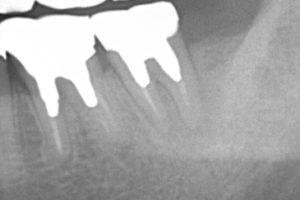

当院の取り組みとして、高倍率の拡大鏡を使用することで、裸眼と比較するとかなり細部まで確認することができます。その結果が、こちらのレントゲン写真。

【術後】

画面向かって一番右の歯です。

全て保険診療です。

ここまで1本の歯にこだわることで、現段階では抜歯せずに差し歯をすることが可能になりました。根管治療(歯の根の治療)の再治療はとても困難を極めることが多く、正直、全ての歯を治癒させることは難しいと感じております。

ただ、様々な最先端の方法・道具を駆使することで、保険診療でも当院ではここまで対応できるのです!